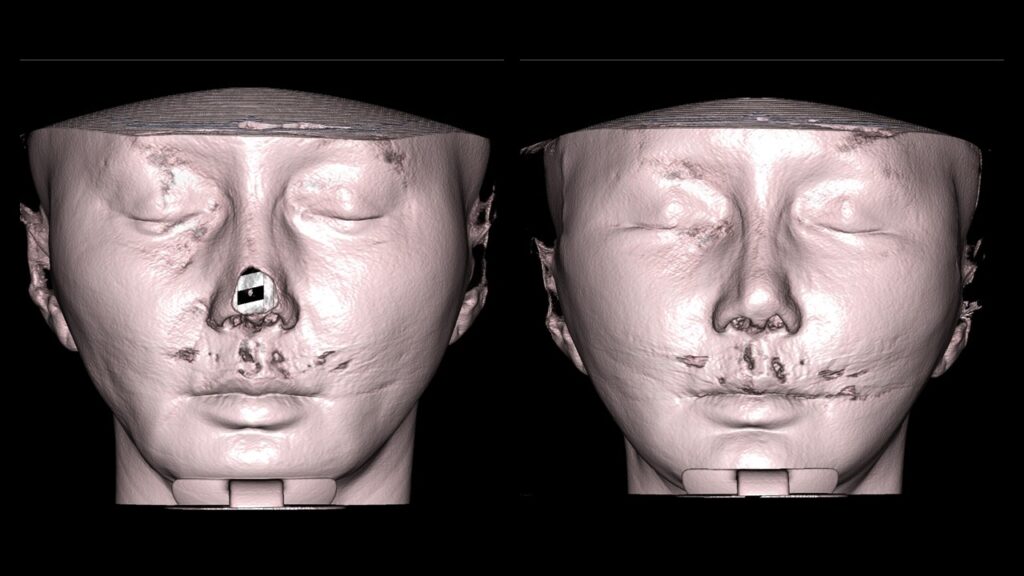

4. Case Studies (3DCT & Medical Photos)

-

Case 1: (Zygoma Reduction + Face Lift) 1-year post-op shows a significant reduction in mid-face width and improvement in nasolabial folds.

-

Case 2: (Zygoma + Chin Advancement + Face Lift + Brow Lift) Dramatic improvement in the side profile and double chin within just 1 month.